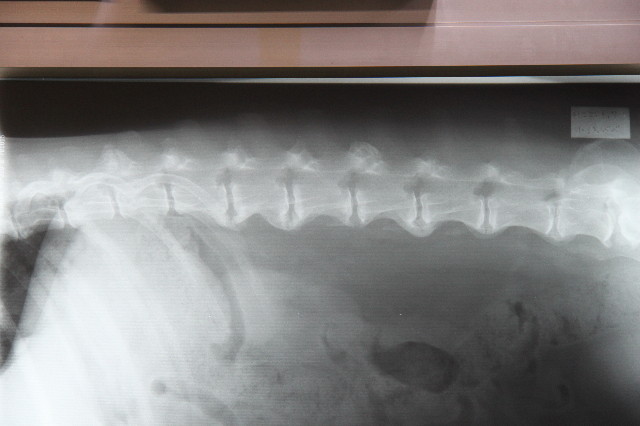

●レントゲンの結果

背骨の5番6番7番(あばらのあたり)と腰骨あたりが以前から変形性脊椎症になっていて、変形した骨がブリッジ状につながりつつあったり、つながっていたんだけど、それがふえたみたい。(ブリッジ状になると神経にへんにさわらないので痛みはない。)

で、背骨がブリッジでつながってしまったことによって骨の柔軟性がなくなり、若い子のように背中をクネクネさせたり曲がったり、狭いところでクルンと小回りに方向転換ができなくなるわけ。

これも老化現象のひとつね。